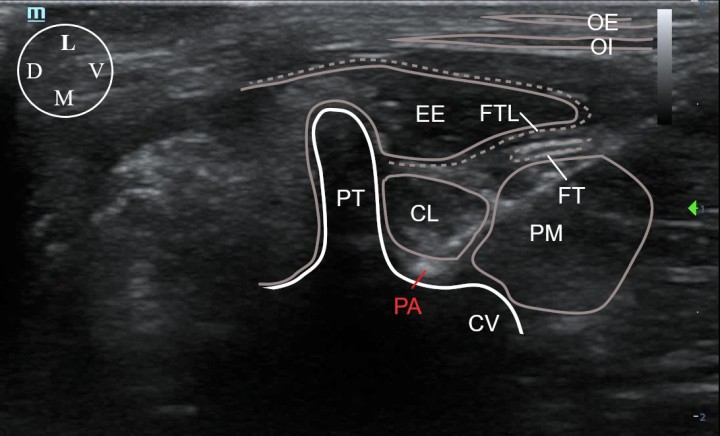

En cirugía abdominal se ha descrito el empleo de técnicas neuroaxiales, como la anestesia epidural, y de bloqueos fasciales, tales como el del plano del cuadrado lumbar, el bloqueo paravertebral torácico, el bloqueo del plano transverso del abdomen y el bloqueo del plano erector espinal. En este caso se realizó un bloqueo guiado por ecografía (Mindray M9 Vet, Mindray Bio-Medical Electronics Co., China) del plano dorsal del cuadrado lumbar (D-QLP) 20 minutos antes de comenzar el procedimiento quirúrgico. Para ello, con el paciente en decúbito lateral y el transductor (14-6 MHz, L14 – 6Ns, Mindray Bio-Medical Electronics Co., Shenzhen, China) posicionado caudal y paralelo a la última costilla y el marcador orientado dorsalmente, se avanzó una aguja espinal (22 G y 63 mm) siguiendo una dirección ventrodorsal mediante una técnica “in plane”, hasta situar la punta de esta en el plano comprendido entre el cuerpo vertebral de L1, su proceso transverso y el aspecto dorsal del músculo cuadrado lumbar. El bloqueo se realizó de forma bilateral inyectando 0,5 mL/kg de bupivacaína al 0,25 % (Bupivacaina B. Braun, B. Braun, Melsungen) a nivel de L1 (Figs. 3 y 4).

<p>Abordaje ecoguiado del plano dorsal del músculo cuadrado lumbar a nivel de la vértebra L1. El transductor fue posicionado paralelo y caudal a la última costilla, con el marcador localizado dorsalmente, y ligeramente orientado en dirección ventrodorsal. La flecha blanca indica la dirección de la aguja empleando una técnica “en plano”. Cr: craneal; Ca: caudal; D: dorsal; V: ventral. La línea blanca discontinua indica la posición de la última costilla.</p>

Figura 3

Abordaje ecoguiado del plano dorsal del músculo cuadrado lumbar a nivel de la vértebra L1. El transductor fue posicionado paralelo y caudal a la última costilla, con el marcador localizado dorsalmente, y ligeramente orientado en dirección ventrodorsal. La flecha blanca indica la dirección de la aguja empleando una técnica “en plano”. Cr: craneal; Ca: caudal; D: dorsal; V: ventral. La línea blanca discontinua indica la posición de la última costilla.